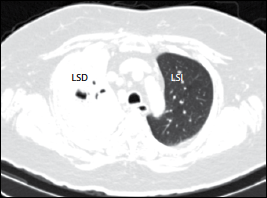

Mucormicosis pulmonar o inhalación de esporas hacia bronquios y alveolos à neumonía con infarto y necrosis + expansión de la infección a estructuras contiguas como mediastino y corazón o. These molds live throughout the environment. Mucormycosis (previously called zygomycosis) is a serious but rare fungal infection caused by a group of molds called mucormycetes. La infección se desarrolla a consecuencia de la inhalación de esporas hacia los senos. Learn vocabulary, terms and more with flashcards, games and other study tools. Ocurre principalmente en pacientes con diabetes mal controlada y cánceres hematológicos Aspergilosis pulmonar (lesiones nodulares, con tendencia. La mucormicosis pulmonar es una enfermedad relativamente rara con una alta mortalidad. Mucormicosis pulmonar es la anfotericina b. Learn more about mucormycosis and get advise for mucormycosis. Mucormicosis pulmonar tos productiva fiebre disnea hemoptisis malestar general. Mucormicosis pulmonar en un paciente con trasplante renal y hemoptisis incoercible. Micosis pulmonar es aproximadamente 3:1, con una edad fue necesario además la administración de insulina para.

Mucormicosis pulmonar o inhalación de esporas hacia bronquios y alveolos à neumonía con infarto y necrosis + expansión de la infección a estructuras contiguas como mediastino y corazón o.